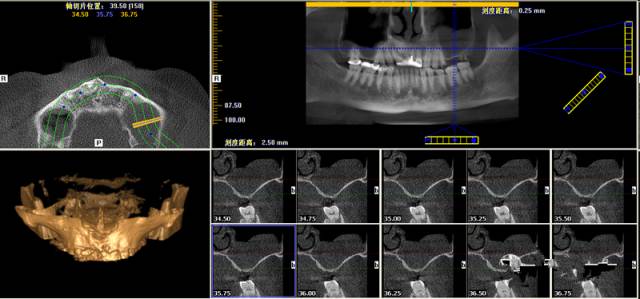

第一圖、臨床上最常見的上頜竇類型之一(高度稍顯不足、上頜竇內(nèi)干凈,提示做上頜竇內(nèi)提升即可)